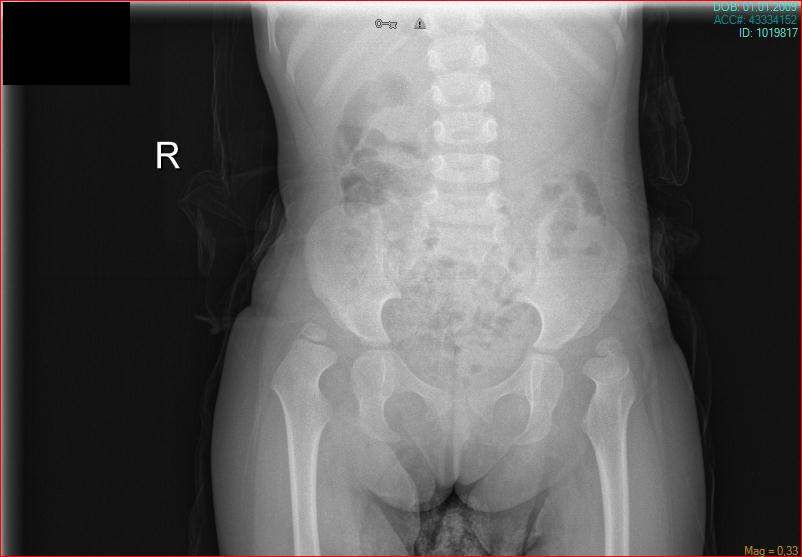

Congenital Pediatric Orthopedic DiseasesDec 30, 2021 | Case ExamplesBilateral GKD Case 1 Bilateral GKD Case 2 Bilateral GKD Case 3 Bilateral GKD Case 4 Congenital Clubfoot Fibuler Hemimeli Tibial Hemimeli PFFD